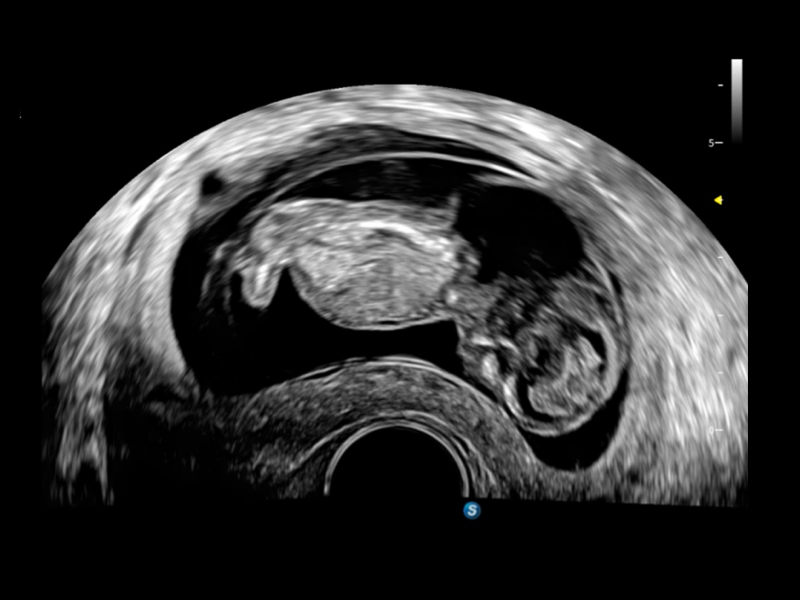

作為開立醫(yī)療全新打造的超高端旗艦超聲產(chǎn)品,從探頭抬起喚醒開啟掃查到多維探頭發(fā)射接收,通過先進(jìn)的場(chǎng)成像發(fā)射、自適應(yīng)聚合重建等技術(shù),基于RF Data原始射頻數(shù)據(jù)在圖像生成、高端功能等方面實(shí)現(xiàn)突破,提供多科室綜合臨床解決方案。

S80 提供多樣化超聲成像技術(shù),可滿足不同科室的需求,在助力掃查診斷和介入治療中發(fā)揮著重要作用。